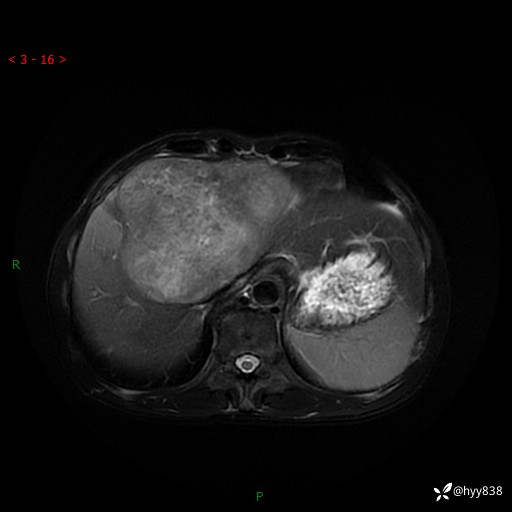

【患者信息】:58岁/男

【主诉】:发现肝占位2天

【现病史及既往史】:患者2天前于当地市第五医院查上腹部磁共振提示:肝脏S4段占位性病变,肝ca可能,胆囊结石,腹膜后多发肿大淋巴结,无剑突下及右上腹疼痛不适,无明显反酸、嗳气,无畏寒、头晕、头痛,无尿频、尿急、尿痛等不适,今为求进一步治疗特来我院就诊,门诊以“肝占位”收住我科。 患者病程中精神、睡眠、饮食尚可,大小便正常、体力体重无明显变化

【检查】:肝脏MRI】平扫+增强